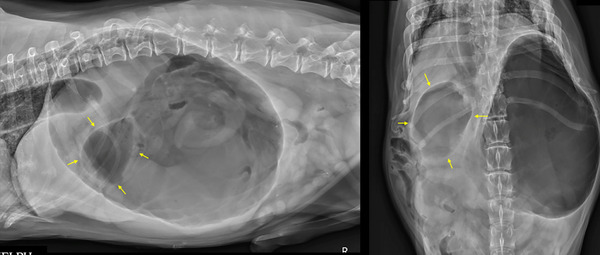

Gastric dilatation and volvulus (GDV) is a life-threatening emergency that requires urgent intervention. Radiographic features associated with 360-GDV in dogs have not been investigated. The aim of this retrospective observational study is to describe radiographic features and clinical variables in dogs affected with 360-GDV and to report agreement rates between different radiologists. We also report the sensitivity and specificity of radiographs to diagnose 360-GDV in dogs. Confirmed 360-GDV cases were retrieved, and the radiographic findings were compared with dogs presenting with gastric dilatation (GD) and 180-GDV. Images were reviewed and graded by three blinded board-certified radiologists. A total of 16 dogs with confirmed 360-GDV were identified. The median age was 10 years old (2-13 years). The sensitivity for detection of 360-GDV ranged between 43.7% and 50%, and the specificity between 84.6% and 92.1%. Interobserver agreement on final diagnosis was substantial (Kappa = 0.623; 0.487-0.760, 95% CI). The highest agreement rate was in cases of 180-GDV (87%), followed by the GD cases (72%) and 360-GDV (46%). Severe esophageal distension and absence of small intestinal dilation were the only radiographic features specifically associated with 360-GDV. A similar pyloric position was found between GD and 360-GDV. Additional radiographic variables that could help differentiate GD from 360-GDV include the degree of gastric distension and the peritoneal serosal contrast. Two cases with 360-GDV were misdiagnosed by the three radiologists as GD. In conclusion, radiographically, 360-GDV cases can reassemble GD and vice versa. Radiologists and clinicians should be aware of the low sensitivity of radiographs for the detection of 360-GDV.

胃扩张和胃内卷(GDV)是一种危及生命的急症,需要紧急干预。目前尚未研究过与犬 360-GDV 相关的放射学特征。这项回顾性观察研究旨在描述受 360-GDV 影响的犬的放射学特征和临床变量,并报告不同放射科医生之间的一致率。我们还报告了诊断 360-GDV 的敏感性和特异性。我们对确诊的 360-GDV 病例进行了检索,并将其影像学结果与胃扩张(GD)和 180-GDV 病例进行了比较。由三位具有盲人资格的放射科医师对图像进行审查和分级。共有 16 只狗确认患有 360-GDV。中位年龄为 10 岁(2-13 岁)。检测 360-GDV 的灵敏度介于 43.7% 和 50% 之间,特异性介于 84.6% 和 92.1% 之间。观察者之间对最终诊断的一致性很高(Kappa = 0.623; 0.487-0.760, 95% CI)。一致率最高的是 180-GDV 病例(87%),其次是 GD 病例(72%)和 360-GDV 病例(46%)。食管严重扩张和无小肠扩张是与 360-GDV 特别相关的唯一影像学特征。GD 和 360-GDV 的幽门位置相似。有助于区分 GD 和 360-GDV 的其他影像学变量包括胃扩张程度和腹膜浆膜对比度。有两例 360-GDV 病例被三位放射科医生误诊为 GD。总之,从影像学角度看,360-GDV 病例可与 GD 病例重合,反之亦然。放射科医生和临床医生应该意识到,放射线检查对 360-GDV 的检测灵敏度较低。